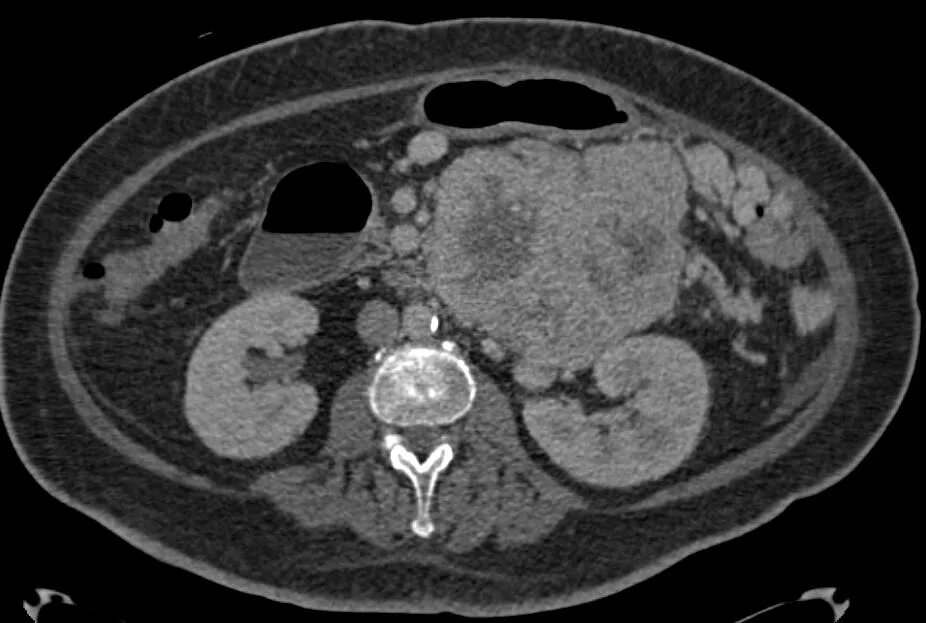

3 метастазы в печени